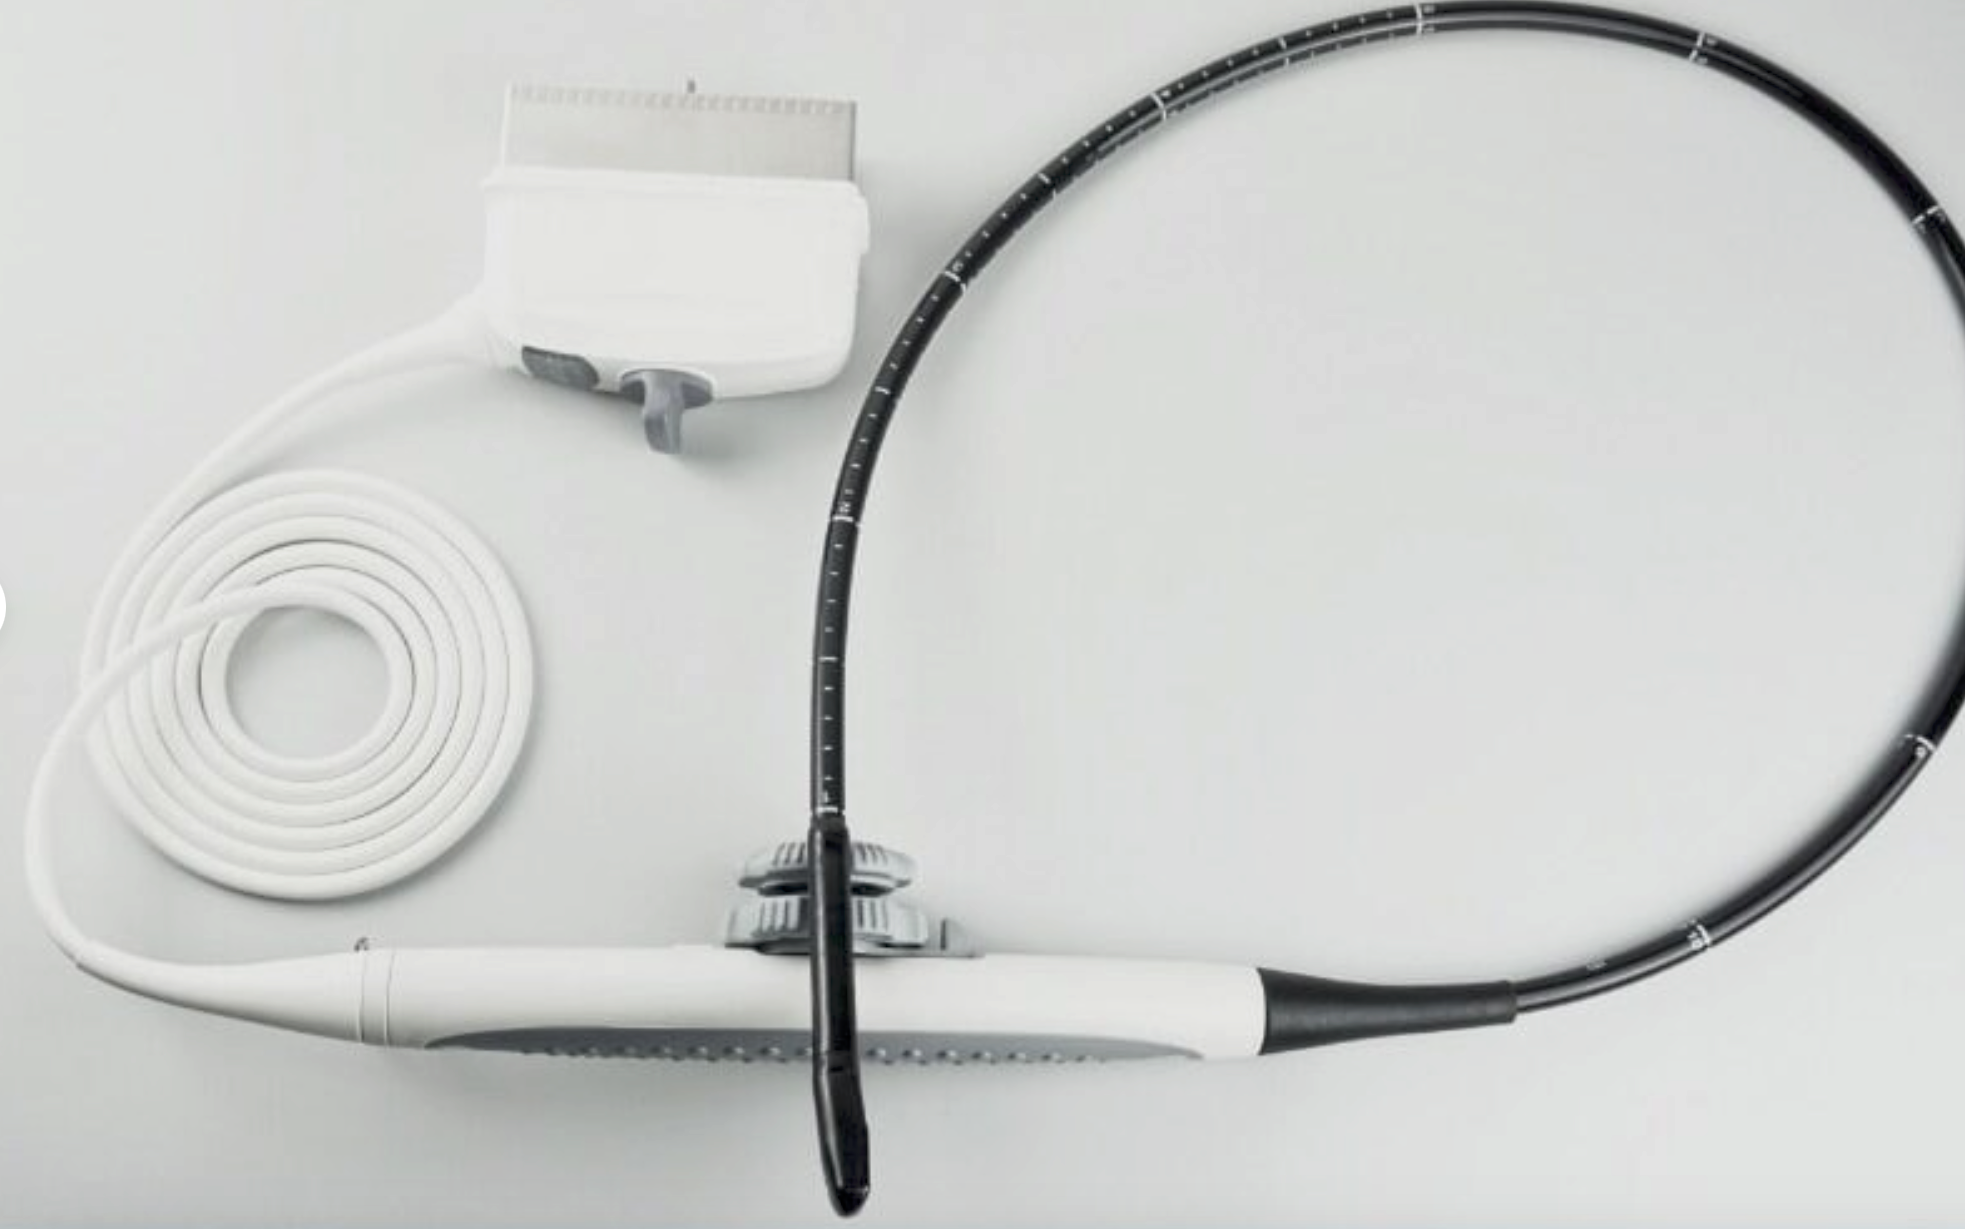

Description

Brand

Philips

MPN

S8-3

Probe is in good condition no compatible ultrasound to test the item. For the power cord, if you see a separate picture of the power cord, you'll receive it. Otherwise, we used the power cord only to test the item.